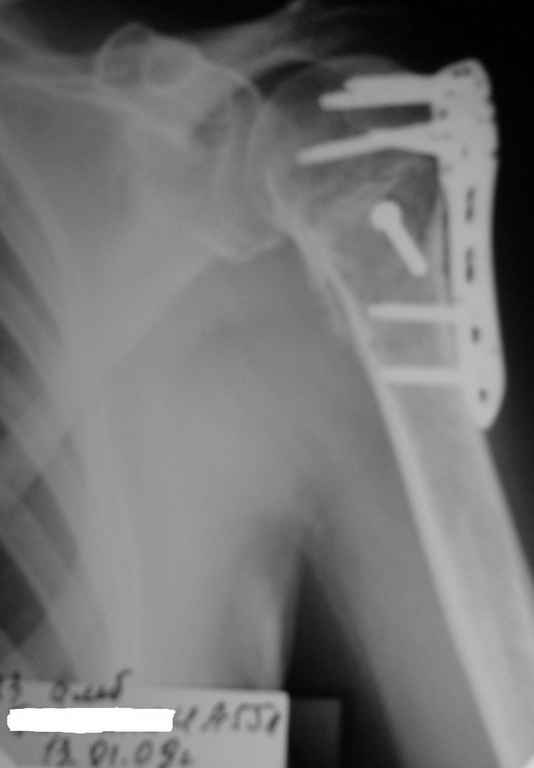

Пациентка Б.1953 г.р., врач-терапевт. Травма 27.11.08г. Падение с высоты роста. Выявлен закрытый не осложненный оскольчатый перелом хирургической шейки левого плеча со смещением. 02.12.08г. оперирована. Выполнена открытая репозиция и остеосинтез пластиной LCP Деост с дополнительной фиксацией отдельно лежащего фрагмента винтом. Послеоперационный период протекал без особенностей, заживление раны первичным натяжением. Швы сняты через 10 дней. Иммобилизация левой верхней конечности клиновидной подушкой 4 недели. По окончании срока – рентген-контроль и умеренная разработка плечевого сустава. В течении месяца функция левого плечевого сустава восстановилась удовлетворительно: поднятие руки до 110 гр., отведение - 90 гр. и до 110 гр. отведение с лопаткой. Отведение руки назад – 20 гр. Наружная и внутренняя ротация – 20 гр. Пациентка по настоянию самостоятельно вышла на работу. 27.03.09 при контрольном осмотре жалоб не предъявляет, болевой синдром в левом плечевом суставе отсутствует. Отведение плеча активно до 90 гр, пассивно с лопаткой до 110 гр., поднятие – 110 гр, отведение назад 20 гр, наружная и внутренняя ротация по 20 гр. На контрольных рентгенограммах отмечается смещение металлоконструкции, ротация головки плеча с приведением дистального отломка на 13 гр. и смещением к зади на 30 гр. Рентгенограммы прилагаются. Ваш взгляд на дальнейшую тактику лечения пациентки?

Ни какой миграции и смещения пластины нет, это изначальные смещения при остесинтезе.

Нет аксиальной проекции сразу после вмешательства. Возможно, никакого значительного смещения нет, все осталось так, как первично сопоставили...и,

Уважаемый Евгений, похоже, что первый и второй Р-снимки выполнены несколько в разных положениях(ротация) плечевой кости, в связи с этим создается впечатление смещения пластины. Остеосинтез выполнен при угловом смещении отломков.Таковым и остался. Данная ситуация была бы очевидна гораздо раньше, если бы при контрольной Р-графии были выполнены снимки в 2-х проекциях.(Не в обиду, сам иногда выполняю только один).